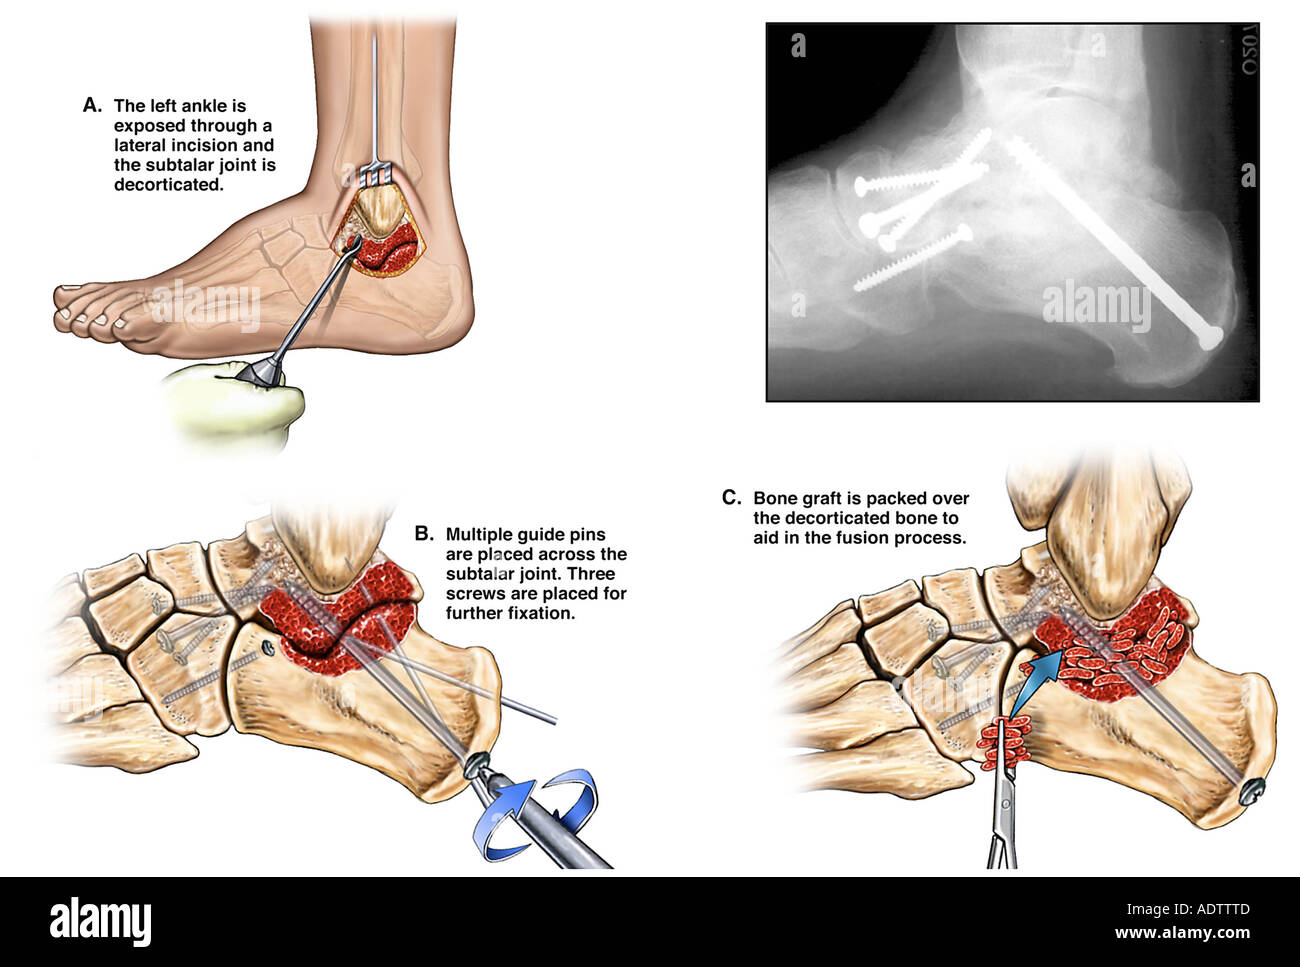

Ankle Fusion Surgery MediVisuals Medical Illustration

medivisuals1.comankle fusion surgery illustration medivisuals1

medivisuals1.comankle fusion surgery illustration medivisuals1

Arthroscopic Ankle Fusion - The Foot And Ankle Clinic

www.thefootandankleclinic.comarthroscopic thefootandankleclinic

www.thefootandankleclinic.comarthroscopic thefootandankleclinic

Ankle Fusion Surgery | One Ashford Hospital | One Hatfield Hospital

ballaratosm.com.auankle arthrodesis triple joint fusion subtalar practitioners providers allied

ballaratosm.com.auankle arthrodesis triple joint fusion subtalar practitioners providers allied